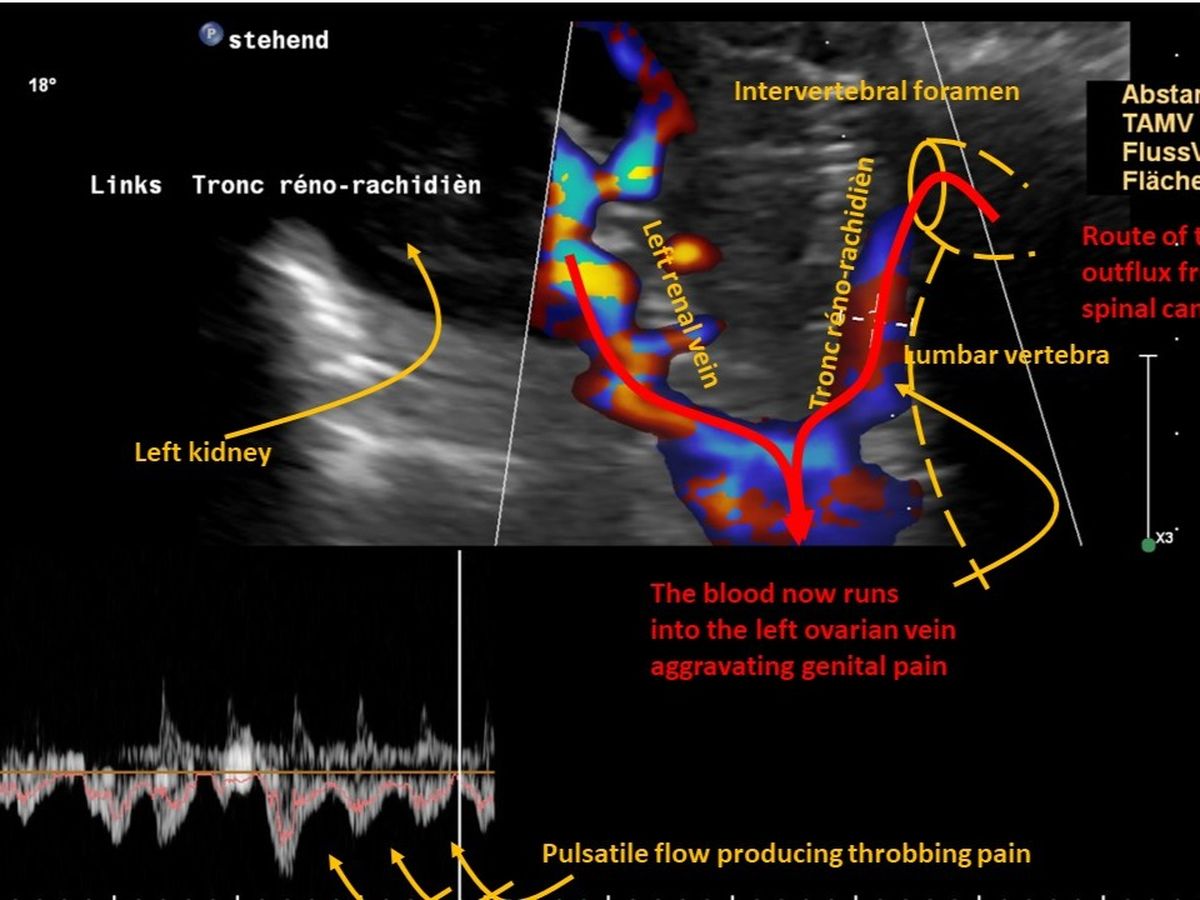

My name is Leah and I've been diagnosed with Abdominal Vascular Compression Syndromes. Unfortunately, these are very misunderstood conditions around the world and the only Dr's that can really help me using more detailed scans and performing major abdominal surgery are located in Germany. The team has very kindly given me an appointment on 17 October 2024 for the scans and 5 November 2024 for the surgery, to take place in Germany. This leaves me with very limited time to try and save enough money for this life-saving procedure. Your donation would go towards the travel, pre-operative scans, surgery, and post-operative care to be undertaken over the course of about six weeks in Germany before I am able to return home.

Sadly I lost my job due to my health, and have been loaded with medical bills from all of my conditions. I have had to pay for scans and appointments with specialists over two hours away by plane to finally be diagnosed with Abdominal Vascular Compression Syndrome's.